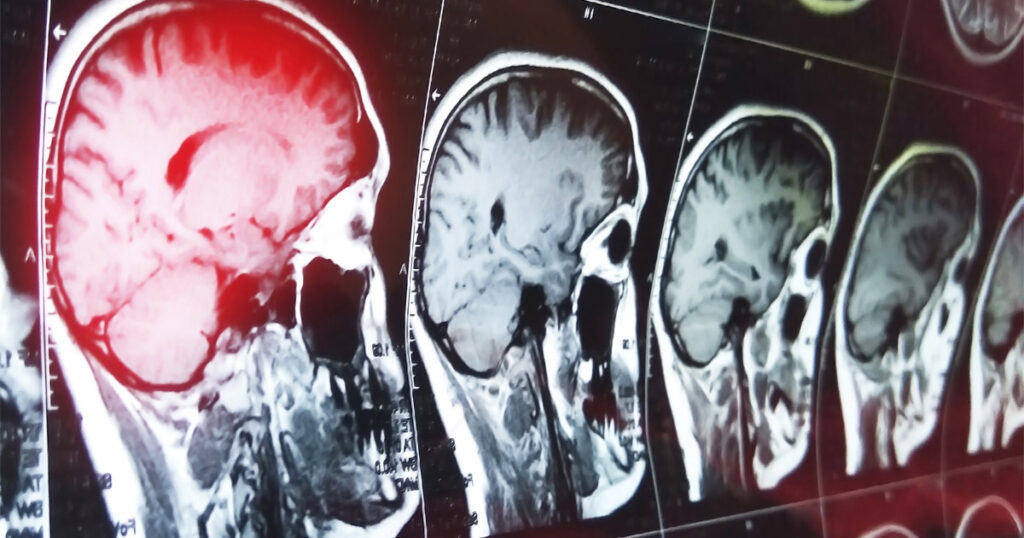

What Are the Types of Traumatic Brain Injuries Caused by a Car Accident?

Traumatic Brain Injuries (TBIs) are among the most serious outcomes of car accidents. They happen during serious crashes as well as seemingly minor ones. These injuries are classified differently, reflecting their cause and symptoms. If you believe that another party caused your TBI in a motor vehicle collision, you might be entitled to compensation. What […]